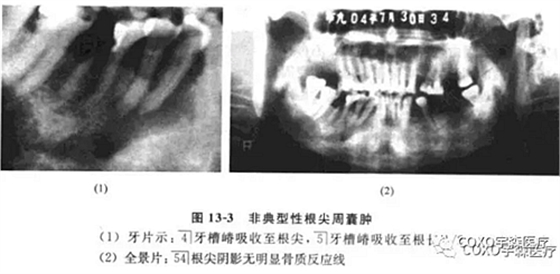

(二)非典型性根尖周囊腫根尖周囊腫的診斷除臨床癥狀外,主要靠X線片檢查。經(jīng)典的診斷標(biāo)準(zhǔn)應(yīng)為在相應(yīng)患牙的根尖部呈現(xiàn)界限清楚的圓形骨質(zhì)稀疏的透射陰影。

周邊可有不同程度白色骨質(zhì)反應(yīng)線;但是不應(yīng)忽略有時(shí)根尖部 線區(qū)表現(xiàn)可以呈非典型性。

病例:女性,72歲,右下牙齦腫脹3周,有牙痛史,外院拍片診斷為“根尖周囊腫”并行頰側(cè)組織切片檢查,病理診斷為“炎癥性病變”轉(zhuǎn)來(lái)我院。

檢查:54]頰側(cè)骨膨隆,頰側(cè)活檢切口無(wú)膿性分泌,54]無(wú)松動(dòng),無(wú)叩痛,6]殘冠、x線片示:654]]冠部均有充填物,4]牙槽骨吸收已近根尖,51]牙槽骨吸收至根長(zhǎng)1/2。全景片示:54]根尖陰影,無(wú)明顯骨質(zhì)反應(yīng)線(圖13-3),54]電活力測(cè)試無(wú)反應(yīng)。

局麻下拔除654],見(jiàn)根尖部有大量肉芽組織予以刮除,術(shù)后傷口順利愈合。病理報(bào)告:右下后牙區(qū)根尖周囊腫,伴反應(yīng)性骨質(zhì)增生。

本病例的臨床診斷為根尖周囊腫,似無(wú)太大疑問(wèn),但X線表現(xiàn)則十分不典型:54]根尖骨質(zhì)呈不規(guī)則、潛穴性吸收,底部幾達(dá)顏孔,更無(wú)明顯骨質(zhì)反應(yīng)線。由于54]無(wú)明顯松動(dòng)及叩痛,加之頰側(cè)骨質(zhì)膨脹,致使牙體牙髓病醫(yī)師疑為腫瘤,不敢進(jìn)行根管治療術(shù)。手術(shù)結(jié)果證實(shí)仍為根尖周囊腫伴反應(yīng)性骨質(zhì)增生。結(jié)合術(shù)中見(jiàn)病灶區(qū)有大量肉芽組織,說(shuō)明本病例的炎癥過(guò)程可能持續(xù)時(shí)間較長(zhǎng),程度較重,致使 線片表現(xiàn)呈不典型性。本例的經(jīng)驗(yàn)是:應(yīng)牢記根尖周囊腫還有不典型表現(xiàn)者,臨床應(yīng)綜合各方面的因素考慮,方能更進(jìn)一步提高臨床診斷水平。